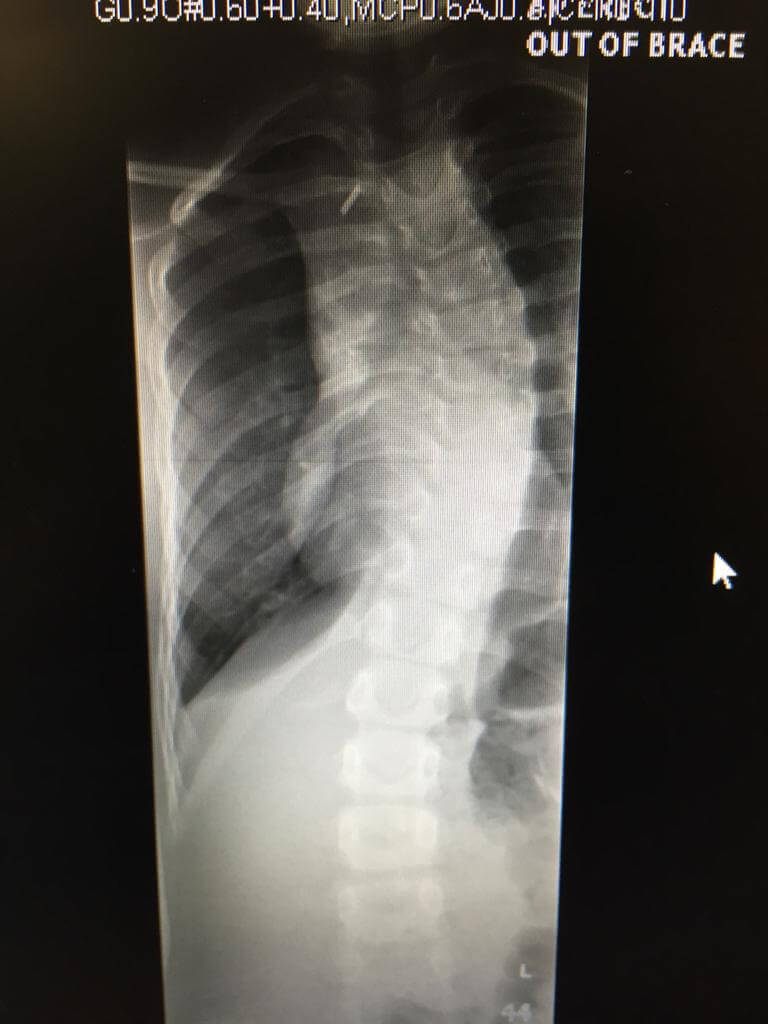

This patient was first seen by Scoliosisuk ltd in September 2017. She was recently seen in 2022 for a review and alterations of her Schroth Best Practice home program as scoliosis continues to need monitoring especially in large growth spurts . Her mum had spinal fusion and both parents are very supportive. She applies short bursts of exercise over 6-12 weeks, reviewing with low dose EOS X-rays and keeping herself super fit with her activities and sports. She has managed the condition without a brace since age 7 and now she is age 12 ! A great example of how to not only avoid surgery but also how to avoid bracing too ! Schroth Best practice can help reverse cobb angle if exercises are carried out well at home with support and the curves are less than 25 degrees. This matches the international guidelines for Scoliosis treatment criteria. Small curves need swift effective action and realistic Schroth programs rather than intensive overwhelming courses of physiotherapy.

‘A young small juvenile curve – uses Schroth Best Practice in short bursts and maintains her activities – avoids not only surgery but also bracing ! From age 7 to age 12!’